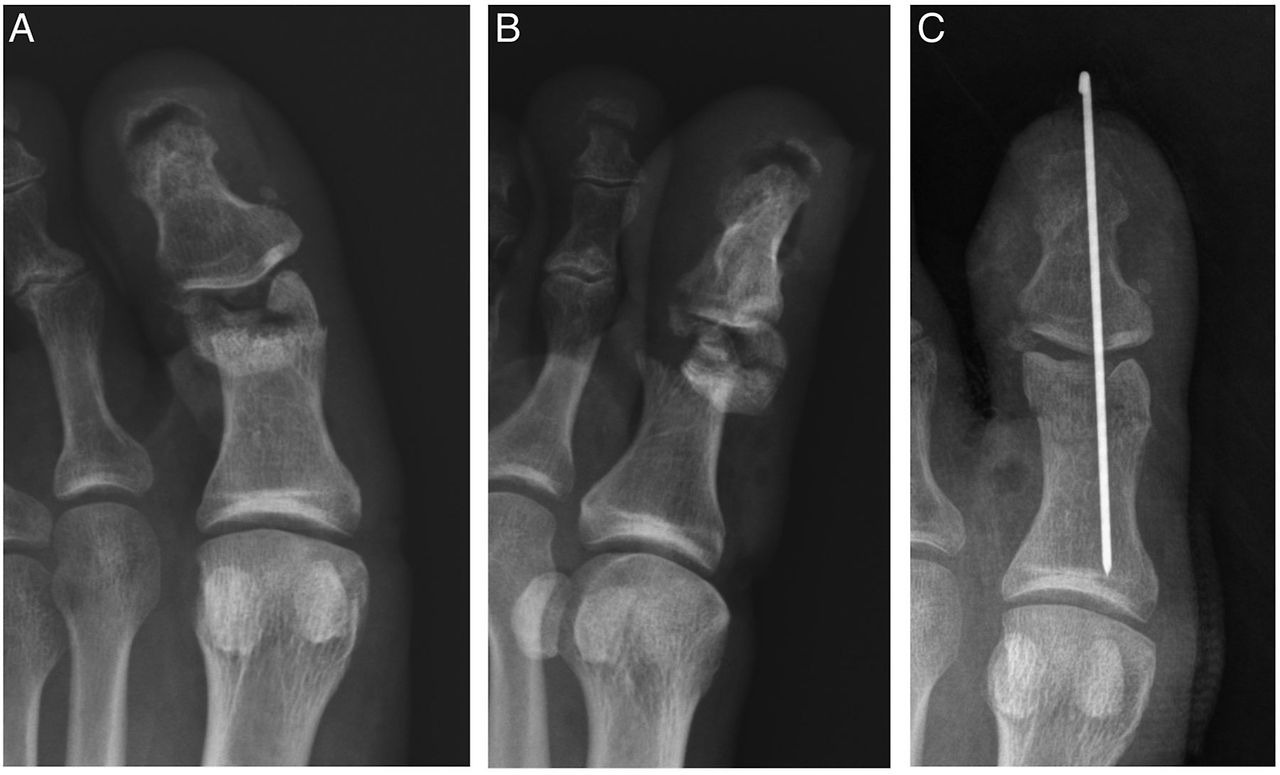

골절 부위가 피부를 뚫고 나와 피가 나는 형태다. 외부 감염 위험이 매우 높아 응급처치와 항생제 치료가 필요하며, 수술이 필수적이다. - 분쇄골절

뼈가 여러 조각으로 부서지는 형태다. 새끼발가락에서 이 경우는 드물지만, 큰 충격을 받은 교통사고나 낙상사고 시 발생할 수 있다.

- 정복: 뼈의 위치가 어긋난 경우, 국소마취 하에 제자리로 맞춤

- 고정: 부목, 깁스, 테이핑으로 3~6주간 고정

- 수술: 금속 핀, 나사, 철심을 이용한 내고정술 시행(개방성·분쇄성 골절 등)